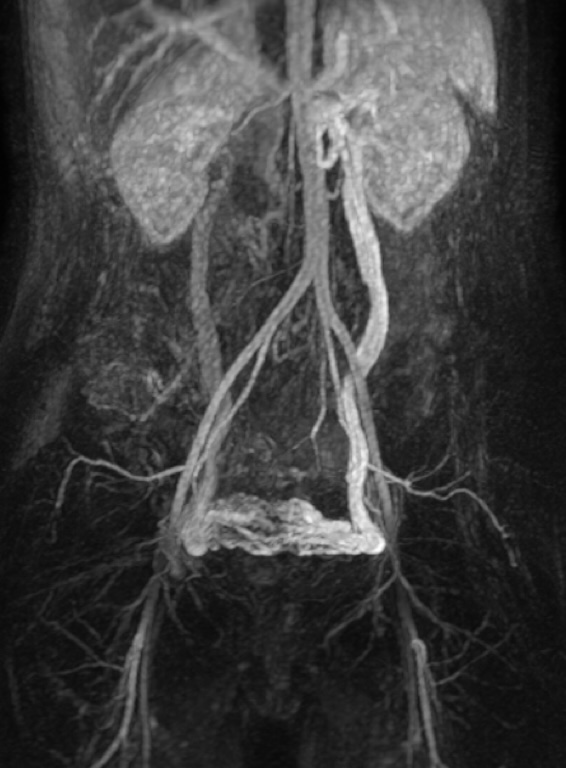

• IRM pelvienne : l'examen de référence permettant également d'éliminer des diagnostics différentiels (endométriose, fibromes, adénomyose, …). Elle permet d'attester le reflux dynamique notamment des veines ovariennes.

Varices pelviennes - IRM